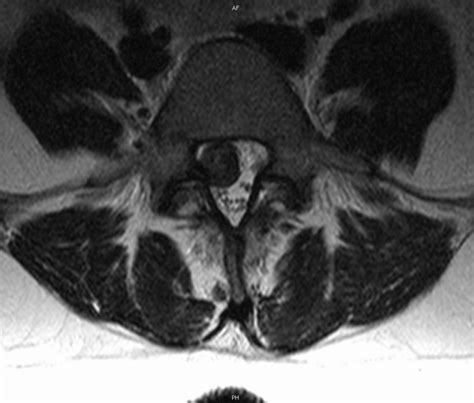

Herniated Disc Treatment - No Drugs or Surgery! | Scottsdale